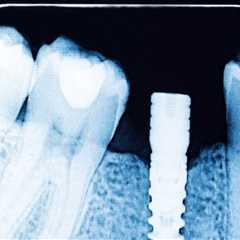

How Dental X-Rays Influence Treatment Planning for Implants and Orthodontics How Dental X-Rays Influence Treatment Planning for Implants and Orthodontics

Dental X-rays have revolutionized modern dentistry by allowing professionals to see what the naked..